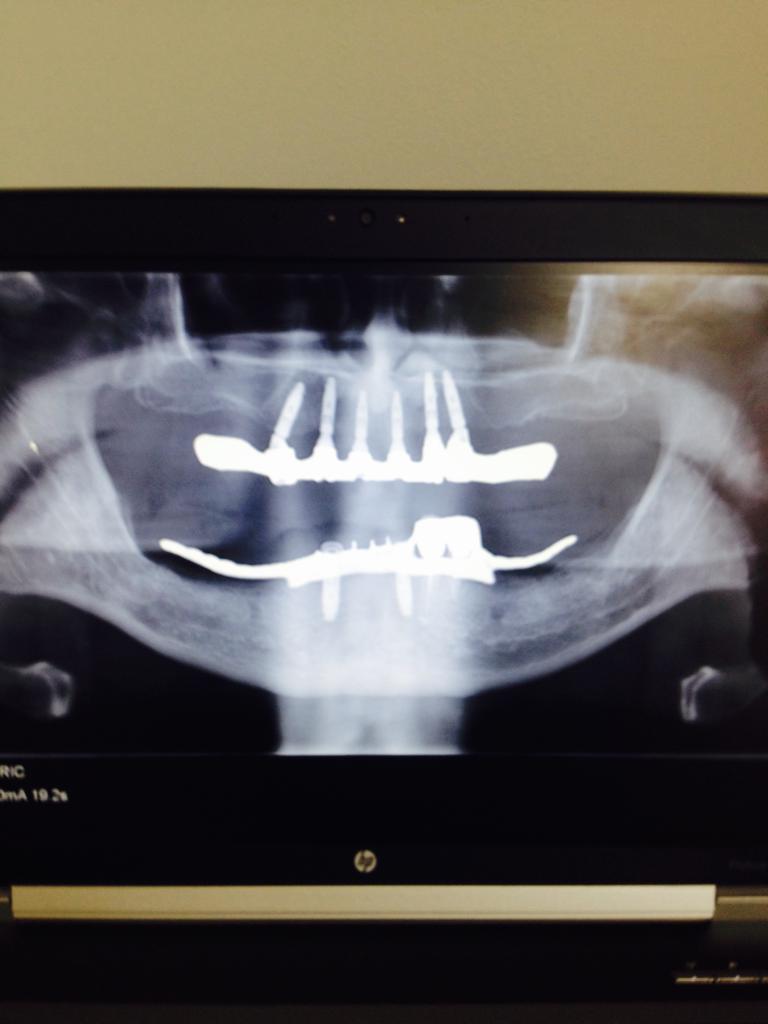

ALL ON SIX

ALL ON FOUR